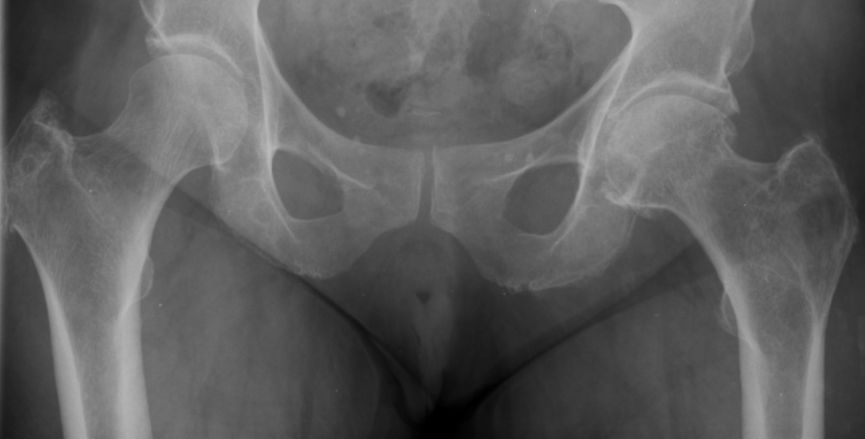

Hüfte |

52-jährige Frau mit exulzeriertem, blutendem

Mammakarzinom T4b N3a M1. Metastasierung des Pfannendachs.![]() | ||||||||||